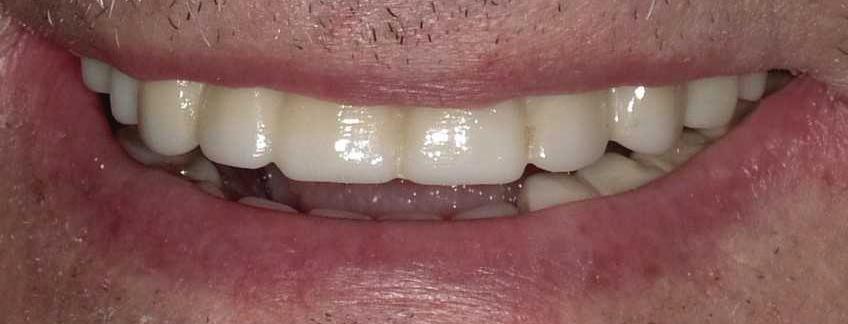

Can just four implants replace all of the teeth on the top or the bottom of your mouth? Thanks to advances in dental implant technology, that answer is a resounding yes.

Believe it or not, tooth loss is extremely common among adults, especially as we age. In fact, more than 35 million people in America are missing all of their upper and/or lower teeth. Rather than living with the discomfort and hassles of dentures, many people are opting for what is called “all-onfour” dental implant restoration.

Here’s where it gets really interesting: You do not need a dental implant for each and every one of your missing teeth. All you need is four precisely placed implants on the top of your mouth, and four on the bottom, to restore your full smile. That’s the beauty of the all-on-four. And because the implant is made of titanium, it has the unique ability to fuse to living bone and function as part of it. So eventually, the dental implant becomes part of the jawbone and serves as a strong, long-lasting foundation for your new teeth.

Thanks to advances in dental implant technology, just four implants can replace all of the teeth on the top or the bottom of your mouth.

this bone fusion has another important benefit: it prevents future bone loss in the jaw. This helps to maintain a more youthful facial structure – and better oral health. But perhaps the biggest surprise about the all-on-four is how quickly it can transform your life.